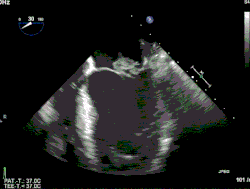

Wissenschaftliche Schwerpunkte von Werner G. Daniel waren die kardiale Bildgebung, insbesondere mittels Echokardiographie und Computertomographie.[7] Er ist einer der Pioniere der transösophagealen Echokardiographie[8] und eine Arbeitsgruppe unter seiner Leitung publizierte die erste wissenschaftliche Arbeit zur Detektion von Koronararterienstenosen mittels eines computertomographischen Verfahrens.